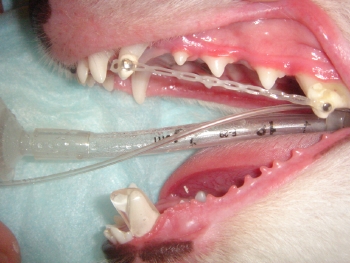

中等度から高度のアンダーショットに対して上顎および下顎の同時矯正を行った一例です。下顎のアンダーに対しては歯の角度を内側(のど側)に上顎に対しては外側(唇側)に歯を捻転させます。この手法は海外のveterinary dentistryの教科書からヒントを得た方法です。ただ海外では中型犬以上が多いためにこのような方法が常に選択肢に入って参りますが、日本では小型犬が多いためにこの方法は使用できないと思われます。もし小型犬でこの方法を用いてしまうと、おそらく矯正終了時には歯に動揺が認められるか、もしそのような事態にはならないとしても歯の寿命を著しく短くする可能性が高いと判断します。以上のことからこのような方法は中型犬以上に用いることが適切と思われます